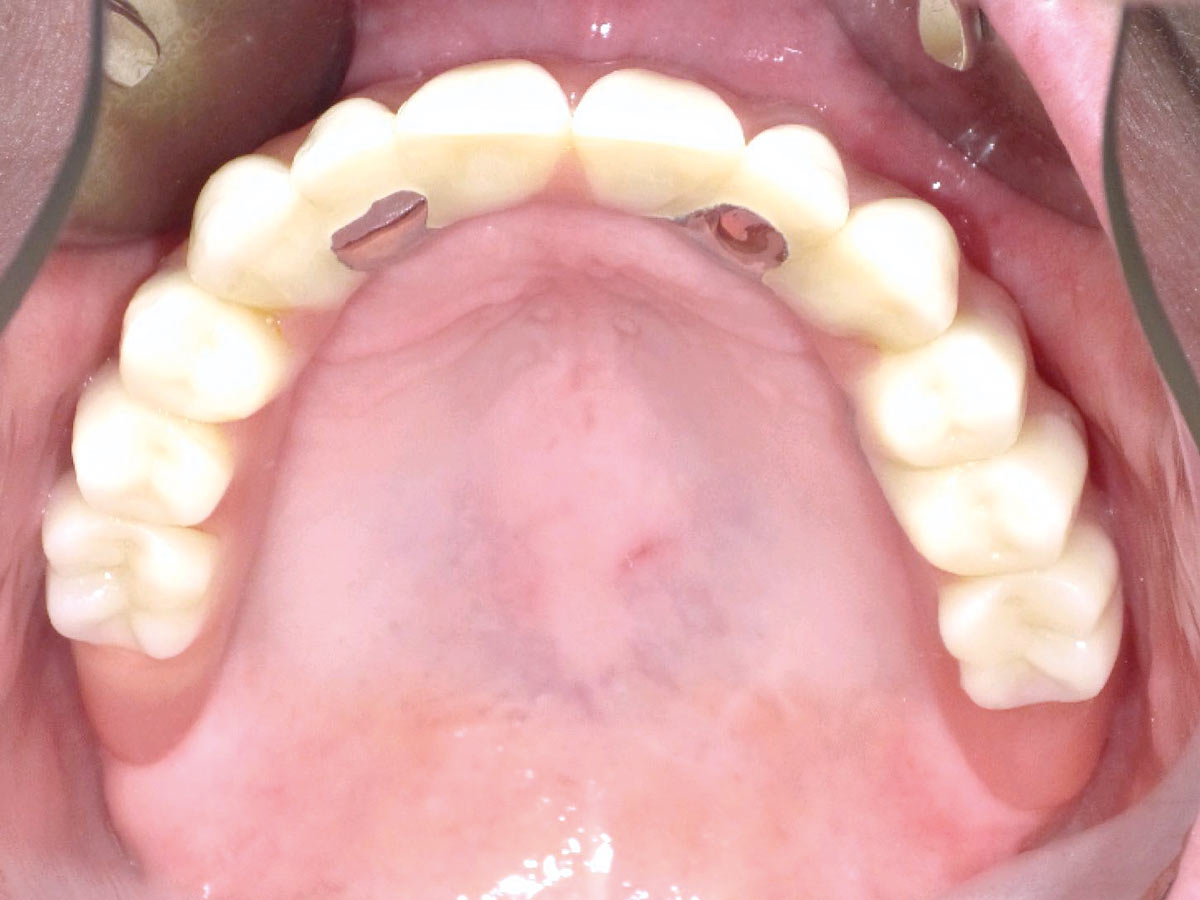

18/23 - Six months follow-up – stable situation

Full arch reconstruction of the maxilla with maxgraft® bonebuilder - Dr. M. Erbshäuser